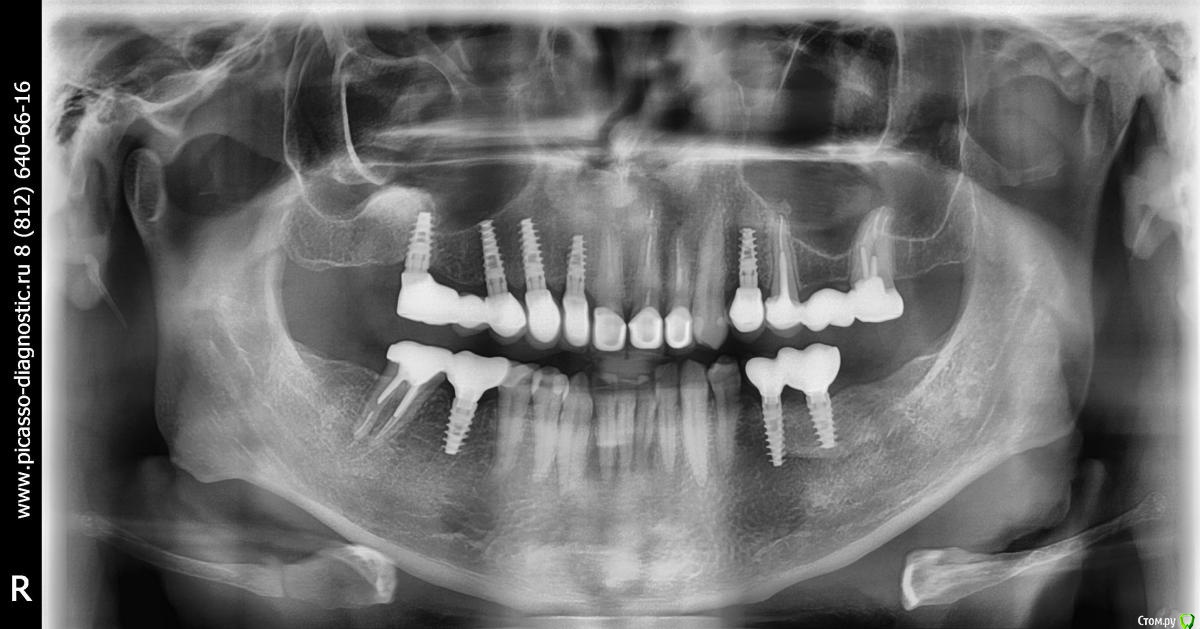

66666 Опубликовано 13 сентября, 2015 Поделиться Опубликовано 13 сентября, 2015 Прошло пол года после окончания лечения. Есть на что обратить внимание? Ссылка на комментарий

66666 Опубликовано 13 сентября, 2015 Автор Поделиться Опубликовано 13 сентября, 2015 а что беспокоит?думал по снимку ясно все будет) если надавить пальцем под носом тупая боль в р-не 21 и 22, реагирует на холод 45. Ссылка на комментарий

IvanK Опубликовано 14 сентября, 2015 Поделиться Опубликовано 14 сентября, 2015 Есть на что обратить внимание? если надавить пальцем под носом тупая боль в р-не 21 и 22, реагирует на холод 45 Вы посещали Своего Врача?Обратитесь к терапевту по поводу 45, к ортопеду - 21,22 Ссылка на комментарий

66666 Опубликовано 14 сентября, 2015 Автор Поделиться Опубликовано 14 сентября, 2015 К врачу записан на субботу. Специально сделал снимок, что б показать на этом форуме. Видимых проблем, я так понимаю, нет? Ссылка на комментарий

red_butler Опубликовано 15 сентября, 2015 Поделиться Опубликовано 15 сентября, 2015 Видимых проблем, я так понимаю, нет? ОПГ всего лишь дополнительный метод обследования. Серьезных проблем не увидел, для остального нужен очный осмотр. Ссылка на комментарий